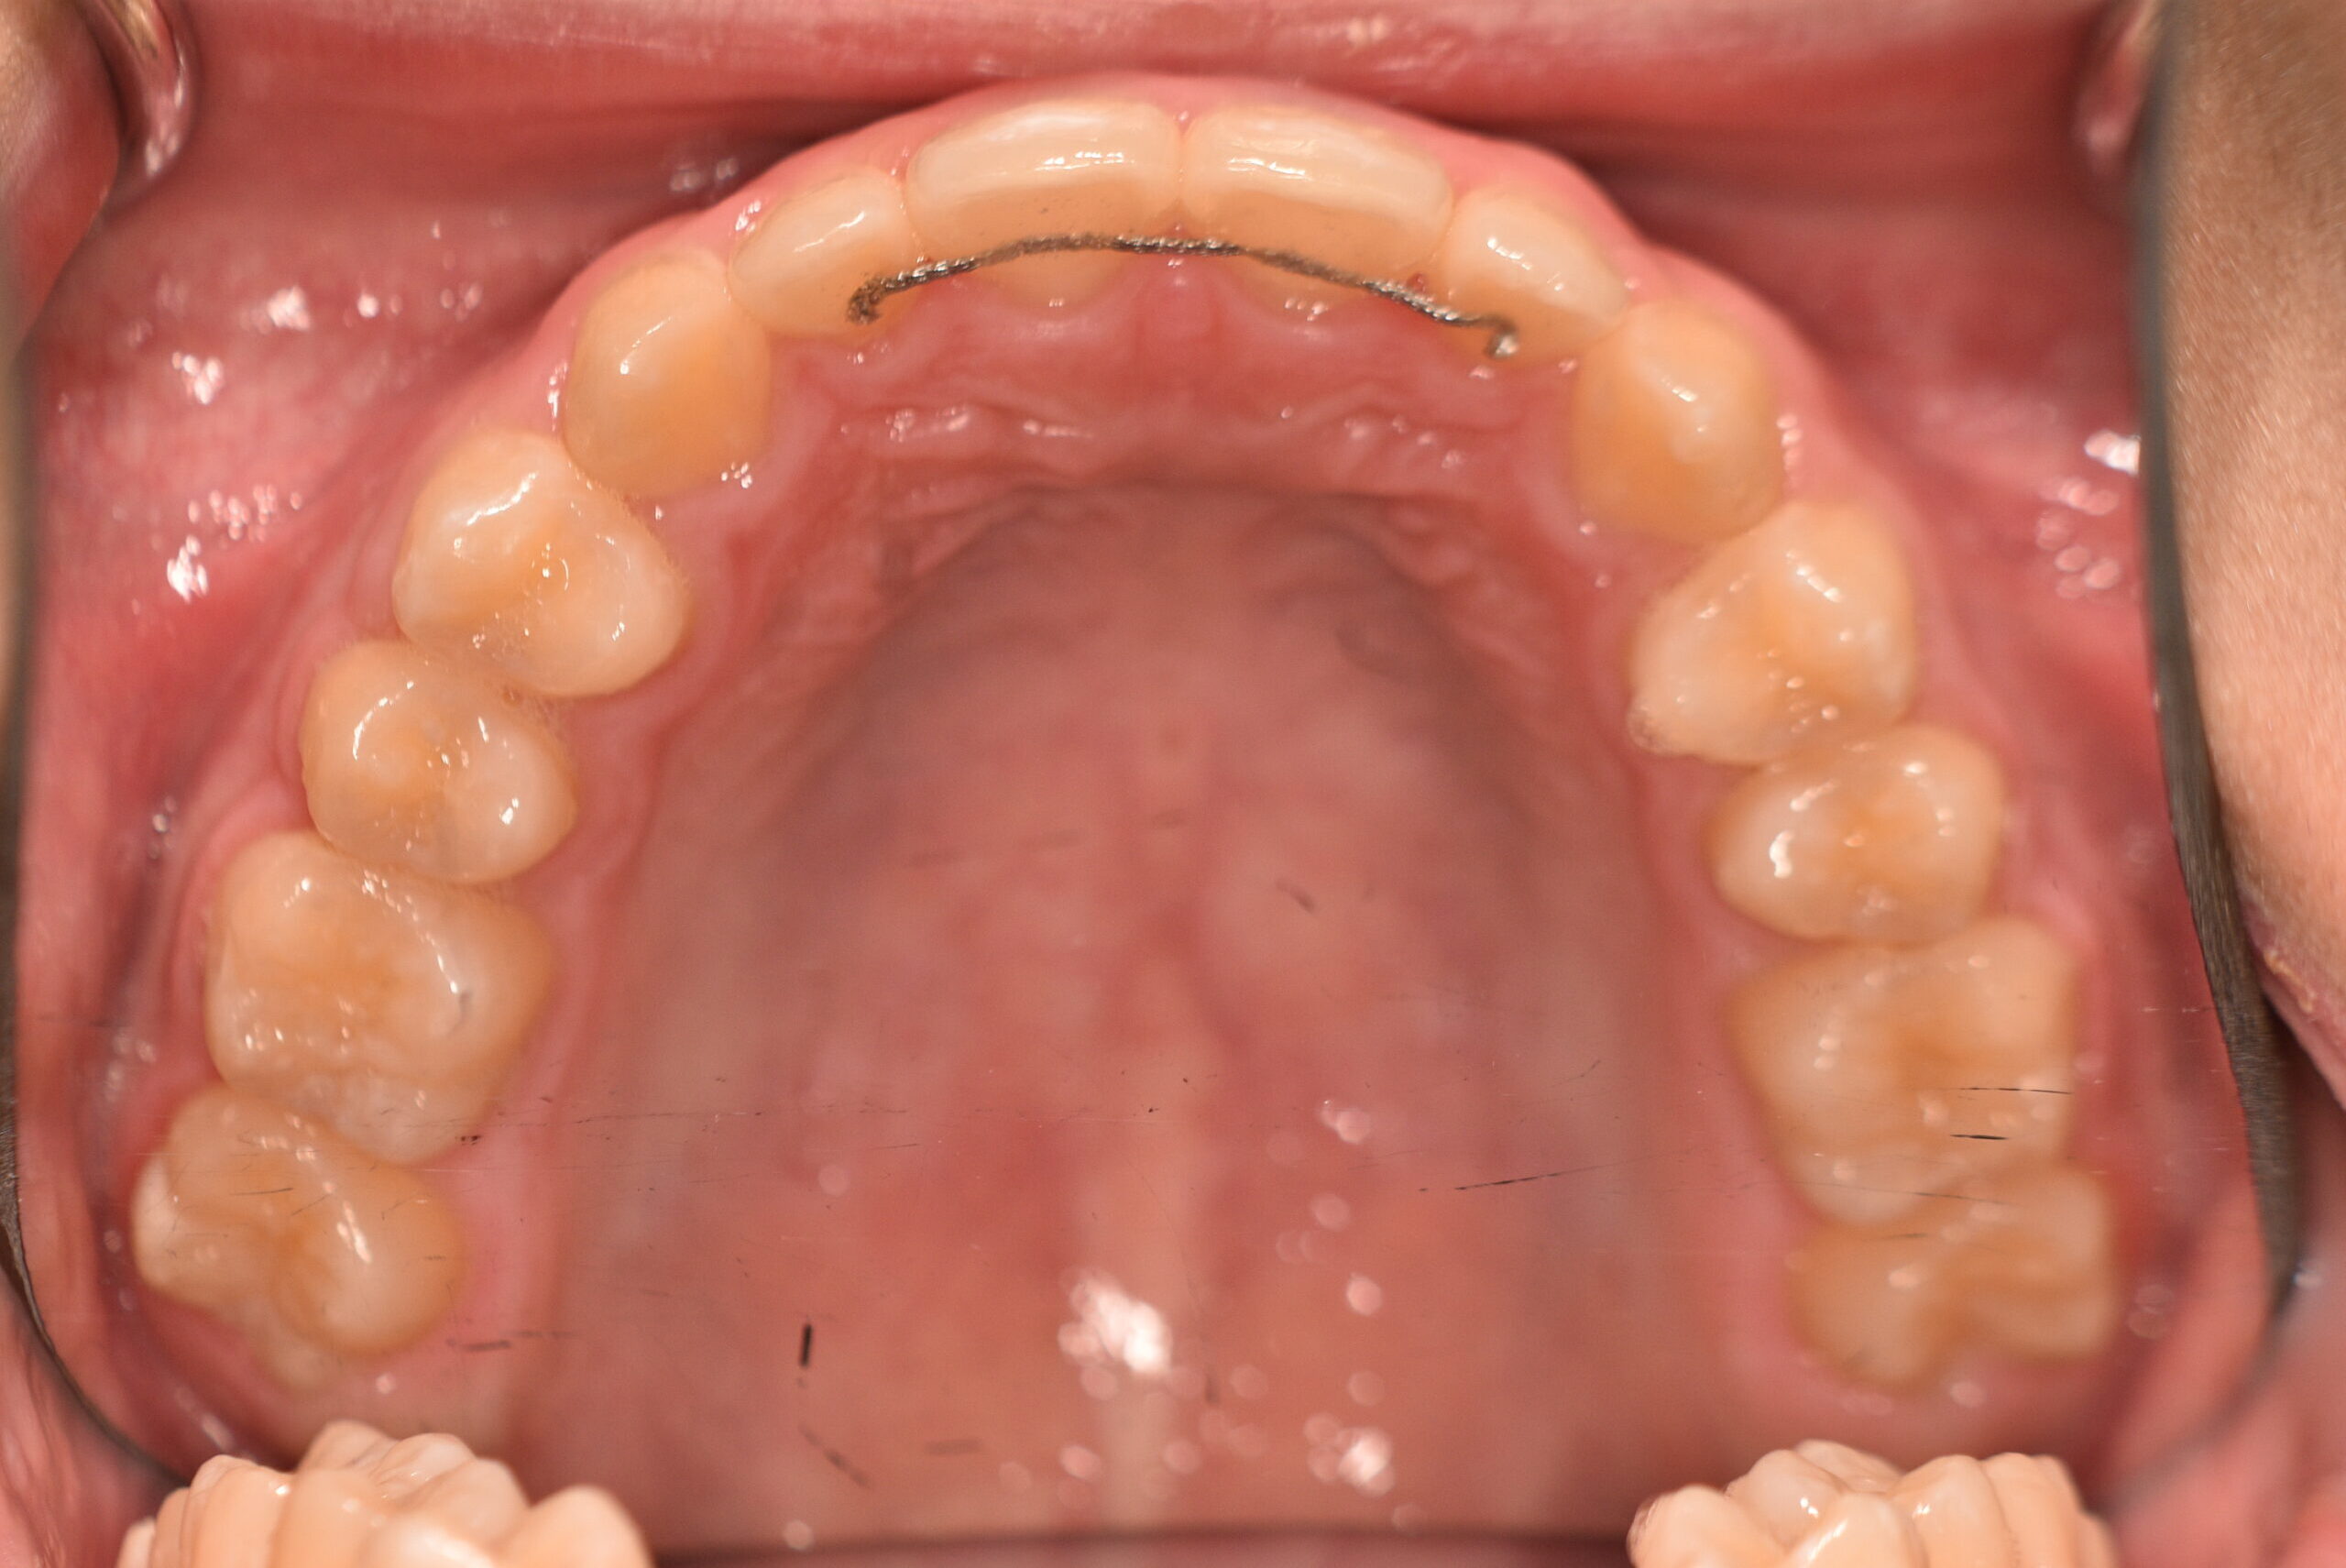

動的治療終了時

症例 症例 症例 症例

永久歯列に交換後、非抜歯の上、セルフライゲーションブラケット装置(デーモンシステム)で歯の配列と咬合関係の改善を行いました。

治療期間は、7年3ヶ月でした。